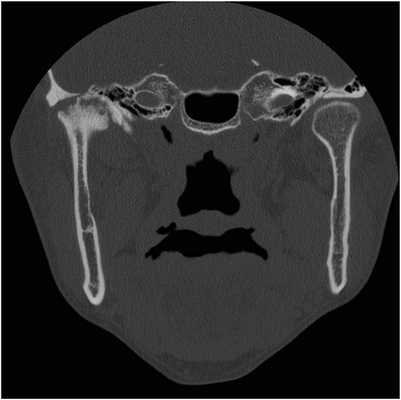

41-летний мужчина, страдающий анкилозирующим спондилитом с 31-летнего возраста, обратился за помощью по причине болевых ощущений в области правого ВНЧС и ограниченного открывания рта (до 25 мм), при котором также наблюдалось отклонение нижней челюсти вправо. В ходе анализа КТ-изображений был заподозрен анкилоз правого ВНЧС, вторичный по отношению к анкилозирующему спондилиту (фото 4).

Фото 4. Корональный КТ-срез, демонстрирующий анкилоз правого ВНЧС.

Для профилактики повторного анкилоза ВНЧС была запланирована реконструкция сустава. Во время операции удалили волокнистую ткань и анкилозированный суставной отросток, обрезали суставную ямку и провели установку протеза. Спустя три месяца после операции открывание рта увеличилось до 36 мм, но челюсть при этом все еще продолжала отклонятся в правую сторону. Ни симптомов воспаления, ни признаков гетеротопического формирования костной ткани в области правого ВНЧС в течение последующего года не отмечалось. Пациент находился под периодическим наблюдением с учетом риска развития анкилоза вокруг установленного протеза, а также вероятности появления патологического очага с левой стороны челюсти из-за анкилозирующего спондилита.